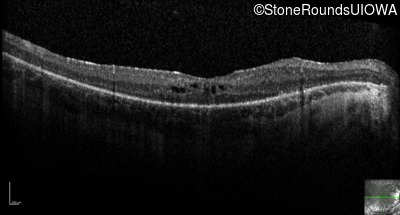

Optical Coherence Tomography - Right - 20/125 sc

Exemplar / OCT Stack